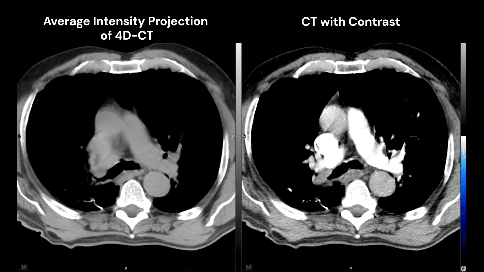

78-year-old male with a 30 pack-year history of smoking and previously diagnosed with Stage IIIA (T4 N0 M0) non-small cell lung carcinoma status post RUL/RLL bilobectomy two years ago and subsequently developed biopsy proven recurrence in right hilar and subcarinal lymph nodes. Definitive chemoradiation to 60 Gray with outback durvalumab is recommended after multi-disciplinary discussion.

The patient has no known history of cardiac disease, but the presence of coronary calcium is noted on the planning CT scans (4D-CT without contrast and free-breathing CT with contrast).

There is growing awareness of the impact of cardiac sub-structure radiation dose exposure on the risk of cardiac injury in lung cancer patients. Historically, the whole heart has been contoured, and the standard of care (such as NCCN guidelines) remains to constrain the whole heart (e.g. mean heart dose < 20 Gy) in the setting of definitive RT for lung cancer. Whole heart dose has been associated with survival (e.g. RTOG 0617), but a survival endpoint is multi-factorial and does not fully capture the cardiac impact of thoracic RT [1]. Emerging data suggests cardiac sub-structure radiation exposure may be more highly associated with specific cardiac toxicity events. For example, intermediate dose to the left-sided coronary arteries (e.g. V15) has been associated with the risk of coronary-related toxicity (e.g. major cardiovascular adverse events including MI, heart failure, coronary stenosis requiring intervention, and sudden cardiac death), while pulmonary vein dose has been associated with the risk of atrial fibrillation [2–5]. Thus, the ability to contour cardiac sub-structures at risk will be an important skill set for lung cancer RT moving forward.Faculty